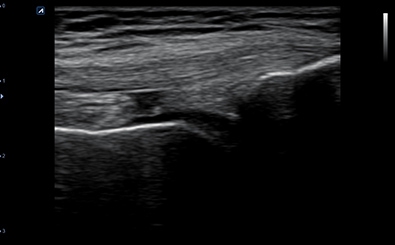

CLINICAL IMAGES

臨床影像

Carotid Artery

Carotid Artery